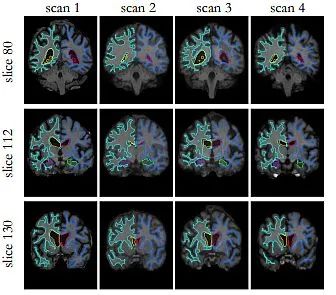

医学成像

医学图像配准旨在找到最佳的空间变换,以最佳地对齐现有的解剖结构。它被广泛应用于许多临床应用中,例如图像重建、图像引导、运动跟踪、分割、剂量积累等。医学图像配准是一个宽泛的主题,可以从不同的角度来考虑。

从输入图像的角度来看,配准方法可以分为单模态、多模态、跨患者和同患者配准。从变形模型的角度来看,配准方法可以分为刚性、仿射和可变形方法。从感兴趣区域(ROI)的角度来看,配准方法可以根据解剖部位分组,例如大脑、肺部配准等。